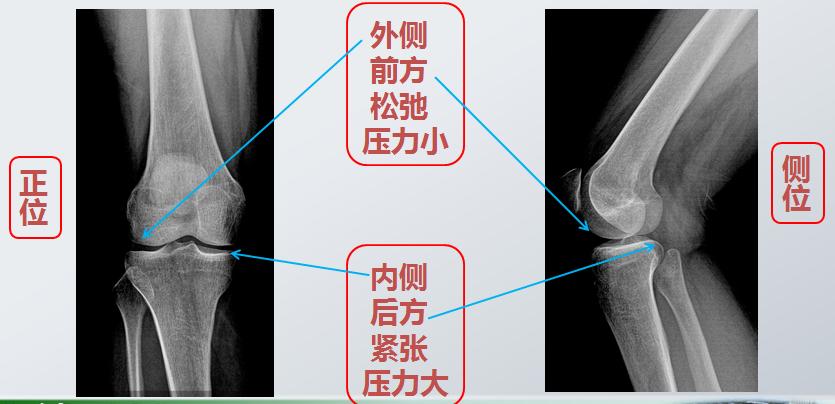

首先,膝关节的磨损最早发生于后内侧

这是因为关节面受力不均的原因

这就是关于膝关节炎的第三个问题

平衡

关节的平衡就像汽车需要四轮定位一样

些许的偏差

就会带来持久的磨损和严重的后果

膝关节后方的肌肉

就像两只手相互交叉拉紧锁定

再加上久坐,膝关节长时间处于屈曲位

后方很容易发生紧缩

所以腘绳肌和腓肠肌都需要拉伸

而前方的肌肉(股四头肌)易出现松弛、乏力

需要加强力量训练

肌力的不均衡不只会带来疼痛

而且由于内侧过紧,

还可能导致“O”型腿的发生

这也是关节炎后期膝关节最常见的畸形